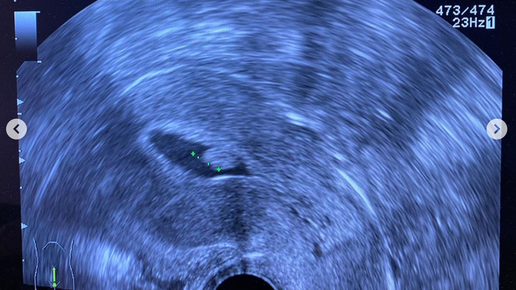

Полип эндометрия представляет собой доброкачественное опухолевидное разрастание внутреннего слоя матки. Находясь внутри полости матки, действует, как инородное тело, как спираль...